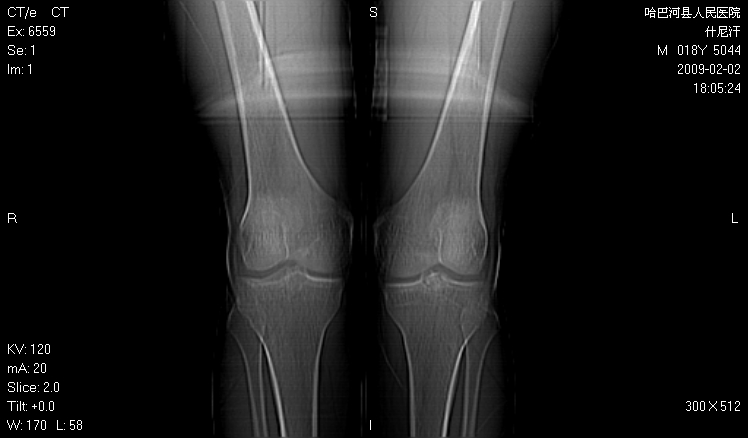

标题: CT17889:外伤后右膝关节反复疼痛3年余 [打印本页]

标题: CT17889:外伤后右膝关节反复疼痛3年余

ct未见明显异常。关节腔未见明显积液,半月板未见明显撕裂。但最好还是mri看看韧带及半月板情况。